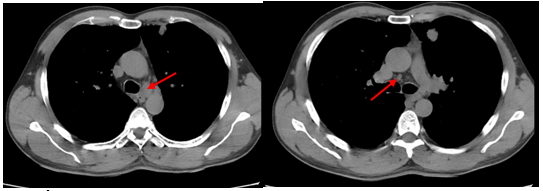

-         Chụp cắt lớp vi tính lồng ngực: phim trước điều trị

Hình 1. Trên phim chụp CT lồng ngực ở cửa sổ nhu mô: thùy trên phổi trái có khối đặc tròn bờ tua gai, kích thước: 29 x20mm, kính mờ và dày kẽ xung quanh, lân cận có nốt bán đặc kích thước 29 x 17mm, ngấm thuốc không đồng nhất sau tiêm, nghi ngờ có phần xâm lấn trung thất trước. Nhu mô thùy còn lại và nhu mô phổi phải lan tỏa các nốt đặc tròn to nhỏ không đều, đường kính: 2-8mm.

Hình 2. Cửa sổ trung thất: Vài hạch trung thất cạnh khí, hạch lớn nhất kích thước 14x7mm

-         Cắt lớp vi tính lồng ngực:

Sau 3 tháng điều trị đích:

U nguyên phát và u thứ phát ở cả 2 phổi đều giảm kích thước rất nhiều, không thấy hạch trung thất.

Sau 6 tháng điều trị:

U nguyên phát chỉ còn kích thước rất nhỏ, u thứ phát 2 bên phổi đã mất hết.